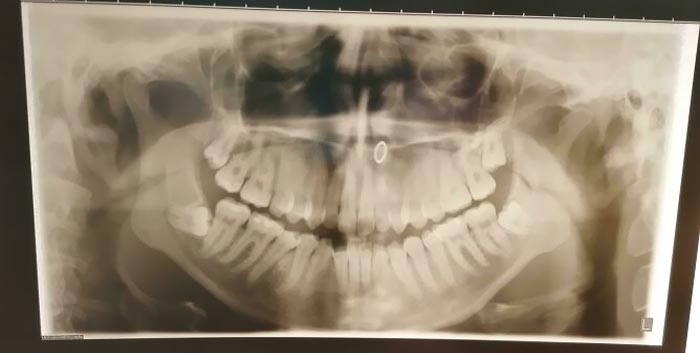

A Piece Of My Infected Wisdom Tooth Just Fell Off

My Wisdom Teeth. No One Wants To Extract Them Because They Could Cut The Alveolar Nerve